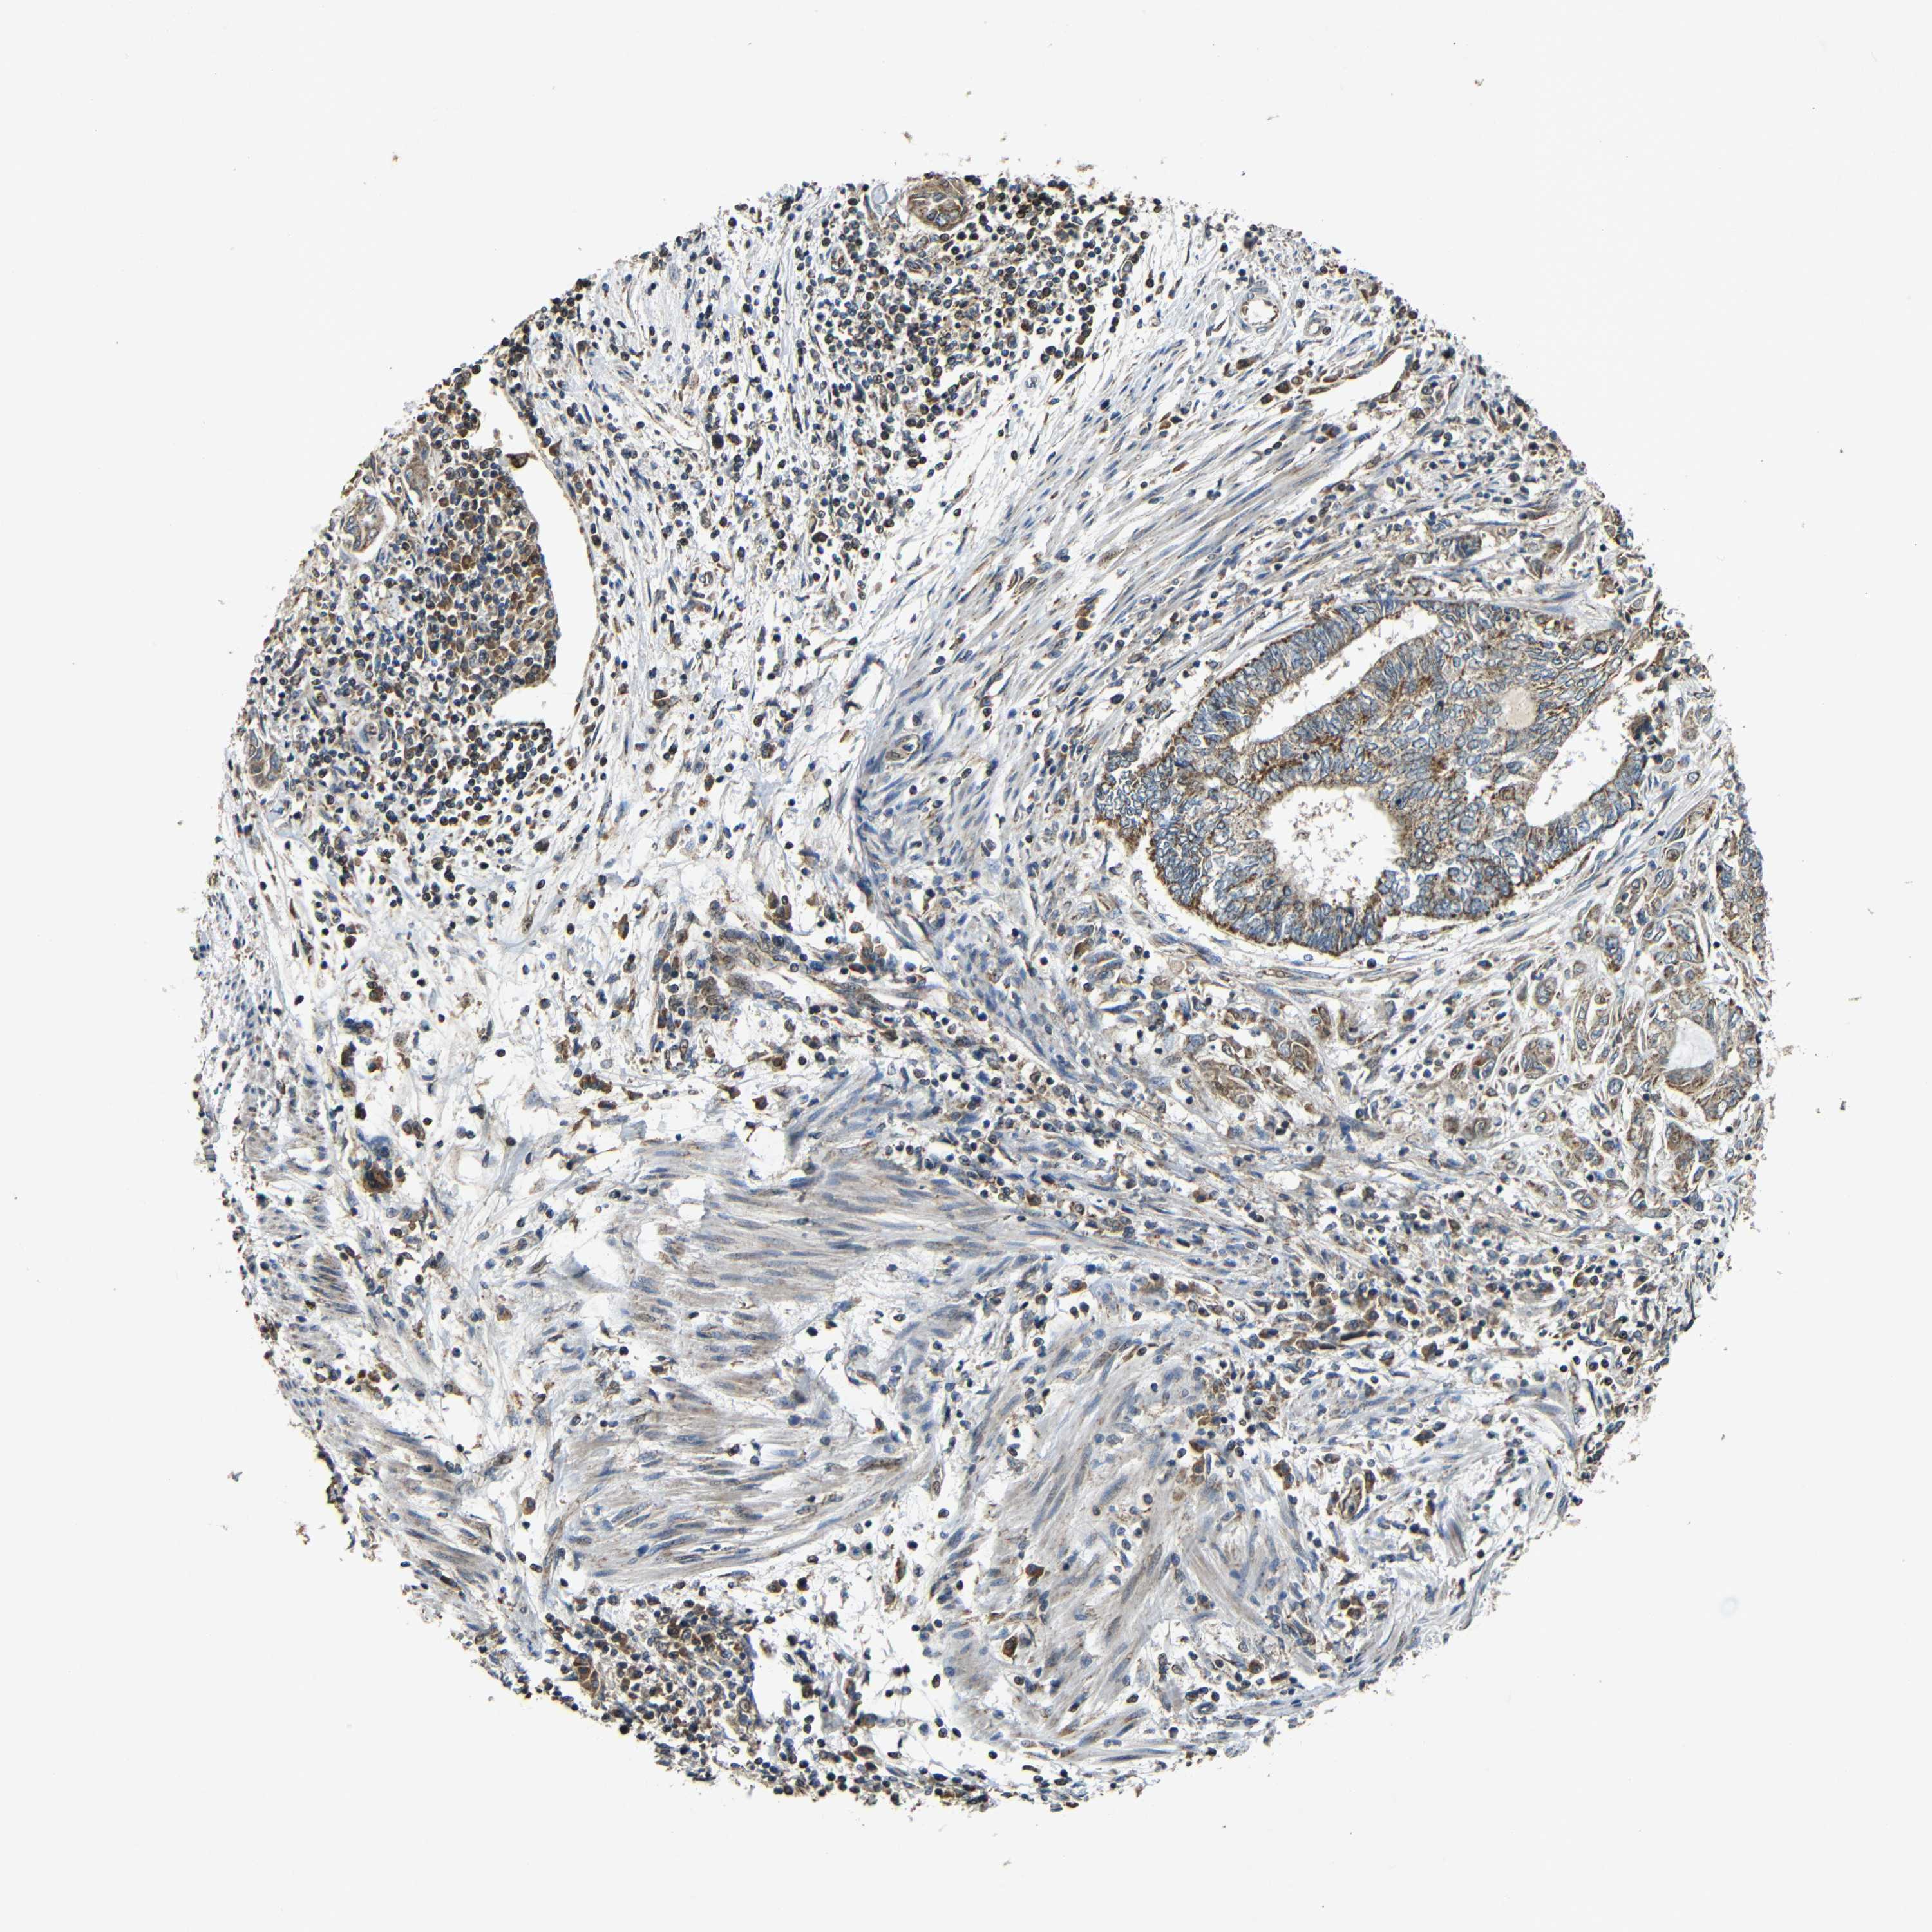

ENDOMETRIAL CANCER - Protein expressioni

A mouse-over function shows sample information and annotation data. Click on an image to view it in a full screen mode. Samples can be filtered based on level of antibody staining by selecting one or several of the following categories: high, medium, low and not detected. The assay and annotation is described here.

Note that samples used for immunohistochemistry by the Human Protein Atlas do not correspond to samples in the TCGA dataset.

Antibody stainingi

Antibody staining in the annotated cell types in the current human tissue is reported as not detected, low, medium, or high, based on conventional immunohistochemistry profiling in selected tissues. This score is based on the combination of the staining intensity and fraction of stained cells.

Each image is clickable and will lead to virtual microscopy that enables deeper exploration of all samples and also displays staining intensity scores, fraction scores and subcellular localization as well as patient and tissue information for each sample.

Antibody HPA011800

Staining

High

Medium

Low

Not detected

Intensity

Strong

Moderate

Weak

Negative

Quantity

>75%

75%-25%

<25%

None

Location

Nuclear

Cytoplasmic/membranous

Cytoplasmic/membranous,nuclear

Adenocarcinoma, NOS